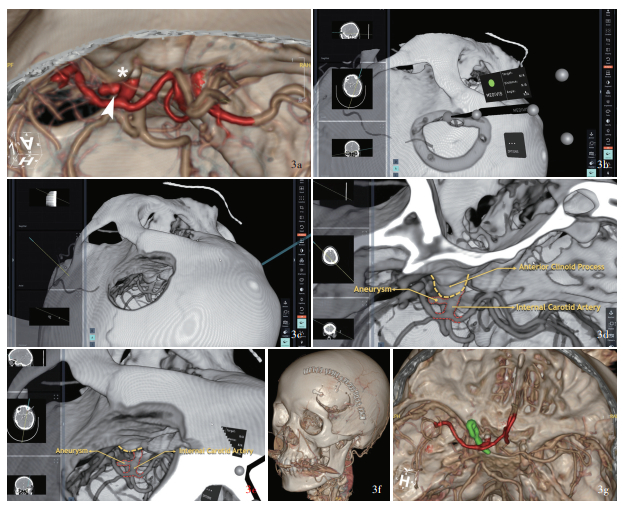

Background: Neurosurgery developed rapidly with technology advancing. Concept of digit-intelligent neurosurgery becomes mature and augmented reality (AR) technology shows great potential in future neurosurgical operations. The feasibility and applicability of AR assisted technology is currently the most important topic in clinical research. Methods: Four cases engaged from January to December 2024 in Department of Neurosurgery of Beijing Tsinghua Changgung Hospital with vestibular schwannoma (one case), intracranial aneurysm (2 cases) and subclavian artery (SA) occlusion caused vertebral artery steal syndrome (one case) have been conducted tumor resection, internal carotid artery (ICA)-posterior communicating artery (PCoA) aneurysm clipping and common carotid artery (CCA)-SA bypass, respectively. Using presurgical imaging data-based Surgical AR reconstruction on the HoloLens 2 platform, preoperative planning, surgical simulation, and intraoperative display were conducted. These were then compared with surgical practices and postoperative imaging data to qualitatively evaluate their effectiveness in assisting neurosurgery. Results: 1) Vestibular schwannoma resection: compared to the preoperative AR assisted simulation, we fully replicated the procedures of retrosigmoid approach craniotomy, removal of the posterior wall of internal auditory canal, and the exposure and removal of the internal auditory canal tumor during surgical practice. Facial nerve function was preserved intact during the surgery and reached House-Brackmann grade Ⅰ, but effective hearing was not preserved. Postoperative imaging data showed non-significant difference compared to preoperative simulation and surgical practice. The modified Rankin Scale (mRS) assessed postoperatively was 2. 2) ICA-PCoA aneurysm clipping: compared to the presurgical AR assistance, we fully replicate the procedures of lateral supraorbital craniotomy, removal of anterior clinoid process and the exposure and clipping of the neck of aneurysm. Postoperative imaging data showed non-significant difference compared to preoperative simulation. Postoperatively symptoms such as eye pain, ptosis, and double visian were completely relieved and the mRS was 0 after 6 months. 3) Basilar artery apex aneurysm clipping: based on preoperative simulation, we opted for the orbito-zygomatic approach during surgery to provide full exposure of the aneurysm neck and direct visualization of the bilateral P1 segment of posterior cerebral artery (PCA), offering better safety compared to the subtemporal approach. In surgical practice, lateral sulcus was separated, basilar artery and aneurysm was exposed and clipped via carotid spaces. Postoperatively occlomoter nerve was well recovered mRS was 0 after 6 months. 4) CCA- SA bypass: critical muscles and vessels on the neck were located intraoperatively on the body surface with AR assistance. CCA and SA were fully exposed and artificial vessel was anastomosed. Postoperative CTA 3D reconstruction suggested the blood flow was patent. The dizziness did not recur, and the blood pressure in the upper limb on the affected side returned to normal. Postoperative mRS was 0 after 6 months. Conclusions: The application of AR technology in neurosurgical procedures allows for preoperative planning, surgical simulation, and intraoperative display. It aids young surgeons in quickly understanding complex anatomical structures and shortens the learning curve, holding significant clinical value and promising application prospects.

研究背景: 计算机技术和人工智能技术的发展使数智神经外科学日趋成熟, 增强现实技术作为新兴技术已在神经外科手术中展现出巨大潜力, 探讨该项技术辅助神经外科手术的可行性和实用性将是现阶段临床研究的重要议题。方法: 纳入4例2024年1-12月在清华大学附属北京清华长庚医院行神经外科手术的前庭神经鞘瘤(1例)、颅内动脉瘤(2例)和锁骨下动脉闭塞致椎动脉盗血综合征(1例)患者, 分别接受前庭神经鞘瘤切除术、颈内动脉-后交通动脉动脉瘤夹闭术和颈总动脉(CCA)-锁骨下动脉(SA)搭桥术; 将术前常规影像学数据导入Surgical AR软件, 基于HoloLens 2平台进行术前规划、模拟手术和术中实时显示, 并与实际手术操作和术后影像学数据对比, 定性分析增强现实技术辅助神经外科手术的疗效。结果: (1)前庭神经鞘瘤切除术: 与术前增强现实技术模拟手术(模拟手术)对比, 实际手术完全复现经枕下乙状窦后入路开颅、内耳道后壁磨除、内耳道内肿瘤显露和切除的操作过程, 术中面神经保护完好, 术后面神经功能达House-Brackmann分级Ⅰ级, 但未保留有效听力; 术后1周三维重建CT与术前模拟和术中实际所见无明显差异; 术后6个月改良Rankin量表(mRS)评分为2分。(2)颈内动脉-后交通动脉动脉瘤夹闭术: 与术前模拟手术对比, 实际手术完全复现经眶上外侧入路开颅、磨除前床突、显露动脉瘤颈并夹闭的手术过程; 术后三维重建CTA与术前模拟无明显差异; 术后6个月, 眼部胀痛、上睑下垂、复视等症状完全缓解, mRS评分为零。(3)基底动脉尖动脉瘤夹闭术: 根据术前模拟结果, 经眶颧入路对动脉瘤颈的显露更充分且术者可于直视下完全夹闭动脉瘤并保护双侧大脑后动脉P1段, 操作安全性明显优于经颞下入路; 实际手术中选择经眶颧入路, 分离外侧裂经颈内动脉-动眼神经间隙显露基底动脉和动脉瘤、夹闭动脉瘤; 术后6个月mRS评分为零, 动眼神经功能恢复良好。(4)CCA-SA搭桥术: 术中通过增强现实技术辅助颈部重要肌肉、血管体表定位, 充分显露颈总动脉和锁骨下动脉, 人工血管吻合; 术后三维重建CTA显示桥血管通畅; 患者头晕症状未再发作, 患侧上肢血压恢复正常; 术后6个月mRS评分为零。结论: 增强现实技术用于神经外科手术可术前手术规划、手术模拟和术中引导, 有助于青年医师快速理解复杂的解剖结构、缩短学习曲线, 具有重要的临床价值和广阔的应用前景。